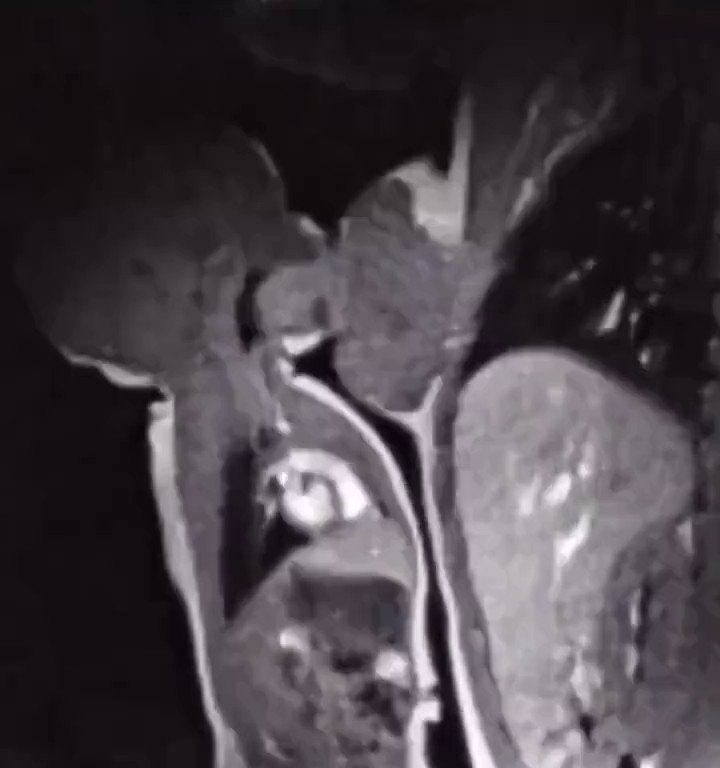

人类哺乳时的核磁共振成像